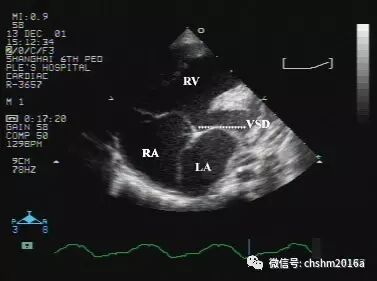

彩超伪像是什么先天性心脏病超声诊断(超声梦影像医生集团 CCM)_https://www.jmylbn.com_新闻资讯_第6张

图2.3.4   室间隔连续中断明显

VSD:室间隔缺损 RV:右室 RA:右房 LA:左房